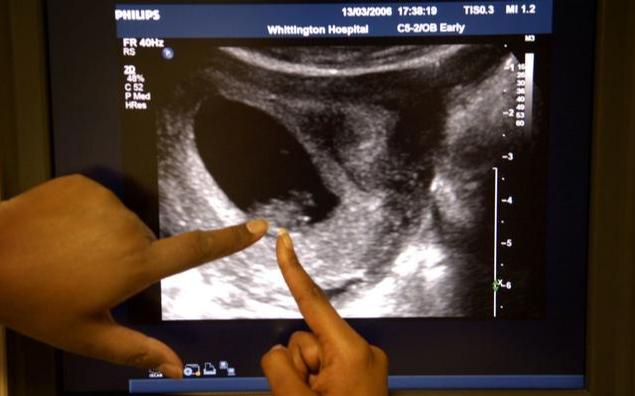

第一个可能就是先兆流产,出血还会伴随下腹隐痛感,一般来说流血的量不是太多,比月经量少,这种时候一定要注意及时就医,通过B超来确定是否为先兆流产;

第二个可能是宫外孕,也叫异位妊娠,胚胎停留在了输卵管上,会有出血、停经、下腹隐痛这些症状,这种情况是非常危险的。

无论是哪种出血,第一时间要做的都是及时就医,通过B超检查来最终确诊,再选择最佳的治疗方案来保住正常发育的胚胎,一定不能掉以轻心,一定不能认为是正常的孕期出血,你不是医生,你的判断是错误的。